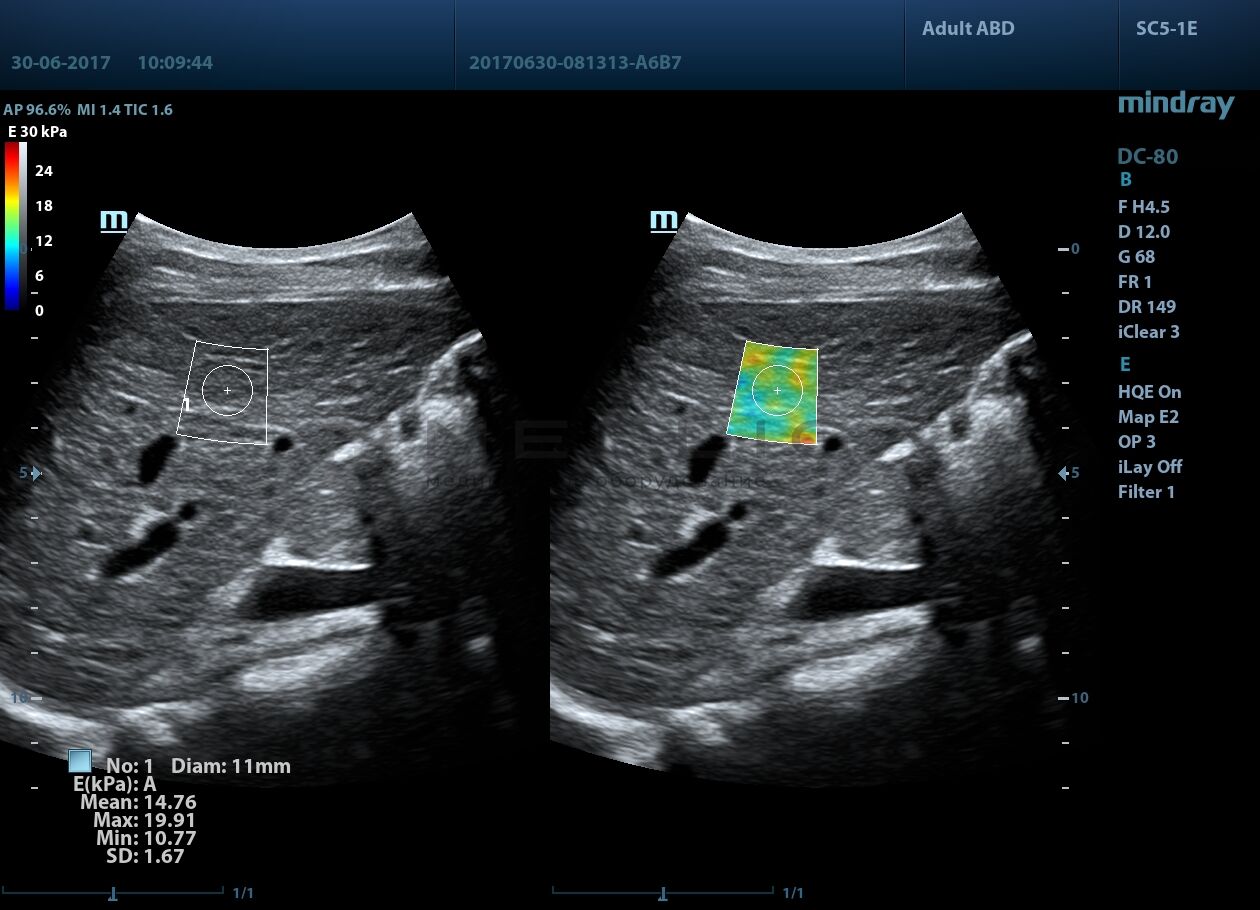

Программное обеспечение для оценки эластичности ткани методом эластографии сдвиговой волны (метод 2D-с формированием двухмерной цветовой эластограммы и количественной оценкой эластичности) на линейных и конвексных датчиках.

STE интегрирована с эксклюзивной технологией Ultra-Wide Beam Tracking от Mindray для двумерной эластографии сдвиговой волной в реальном времени. Специализированные измерительные инструменты позволяют проводить количественный анализ модуля упругости с высокой точностью.

• на линейных датчиках

• на конвексных датчиках